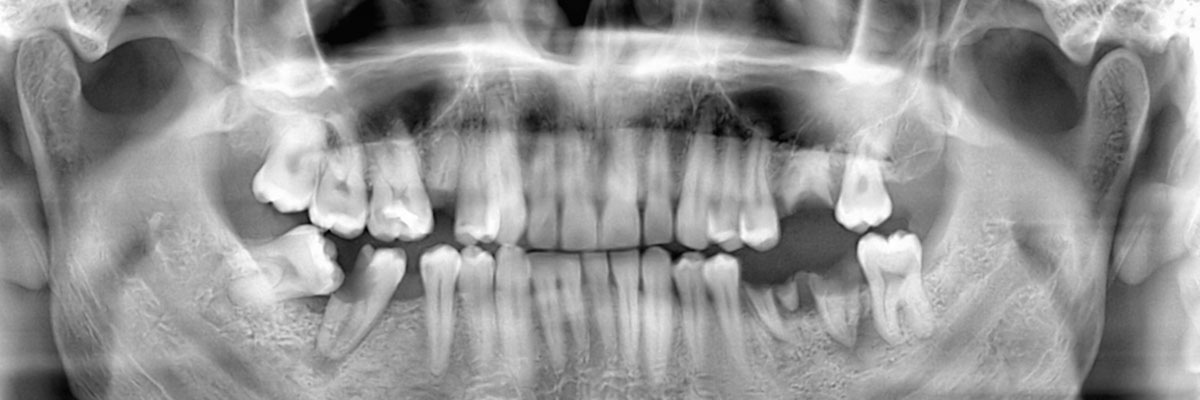

We recommend that you call 330-394-7462 and schedule an appointment with our 44484 dental office as soon as your tooth has either fallen or been knocked out. During your appointment, we will examine your gums, take X-rays, and make a recommendation as to which tooth replacement option will be best suited for your needs. Acting on this quickly will help in restoring your appearance and oral health.